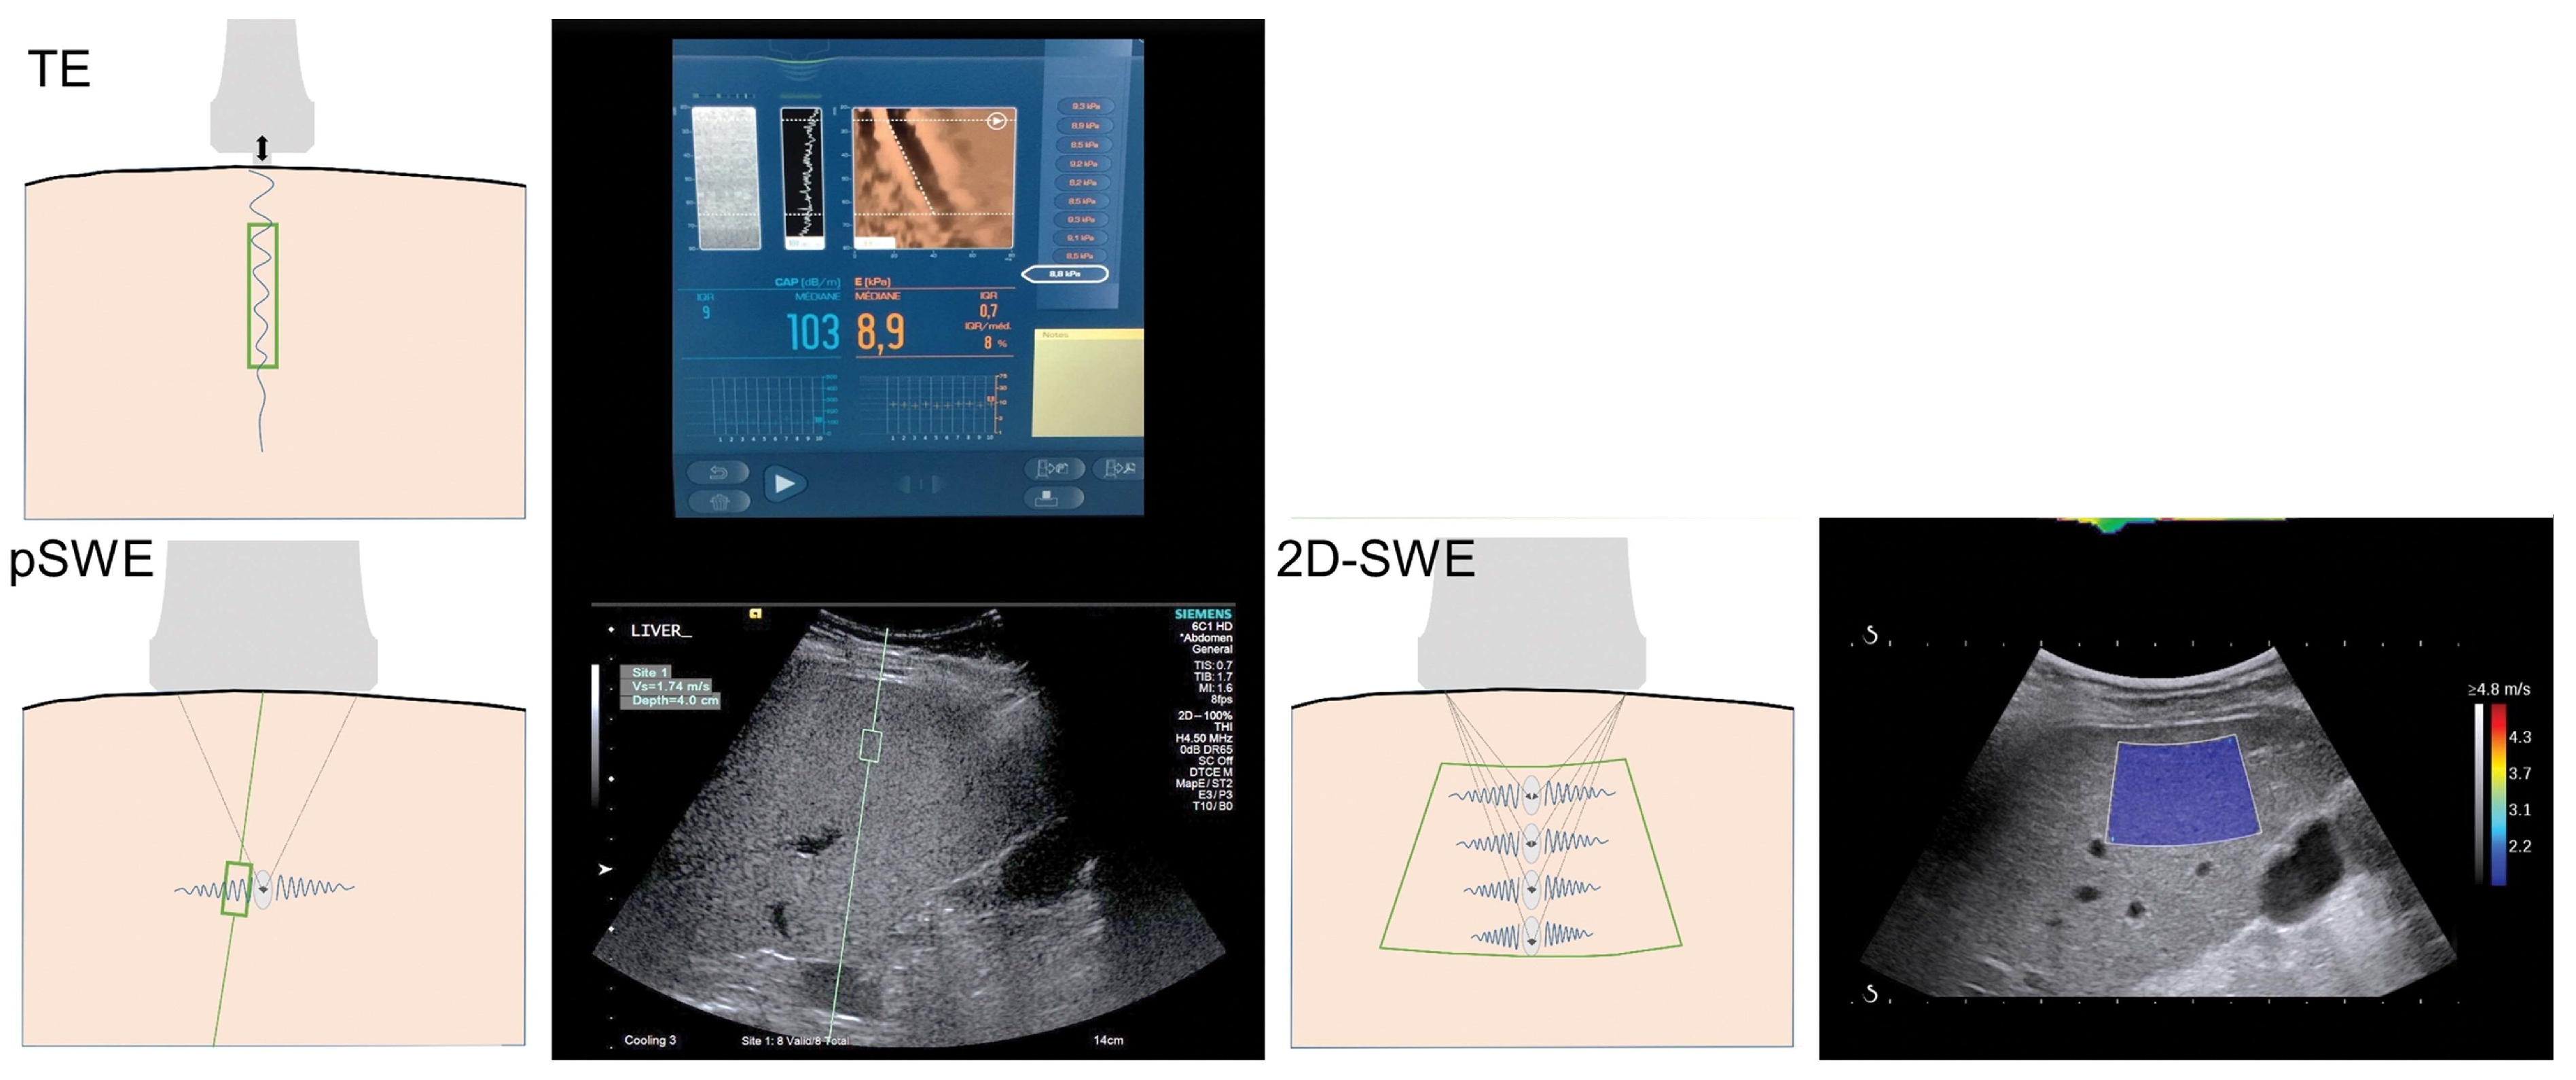

2. Principles of Ultrasound Shear Wave Elastography